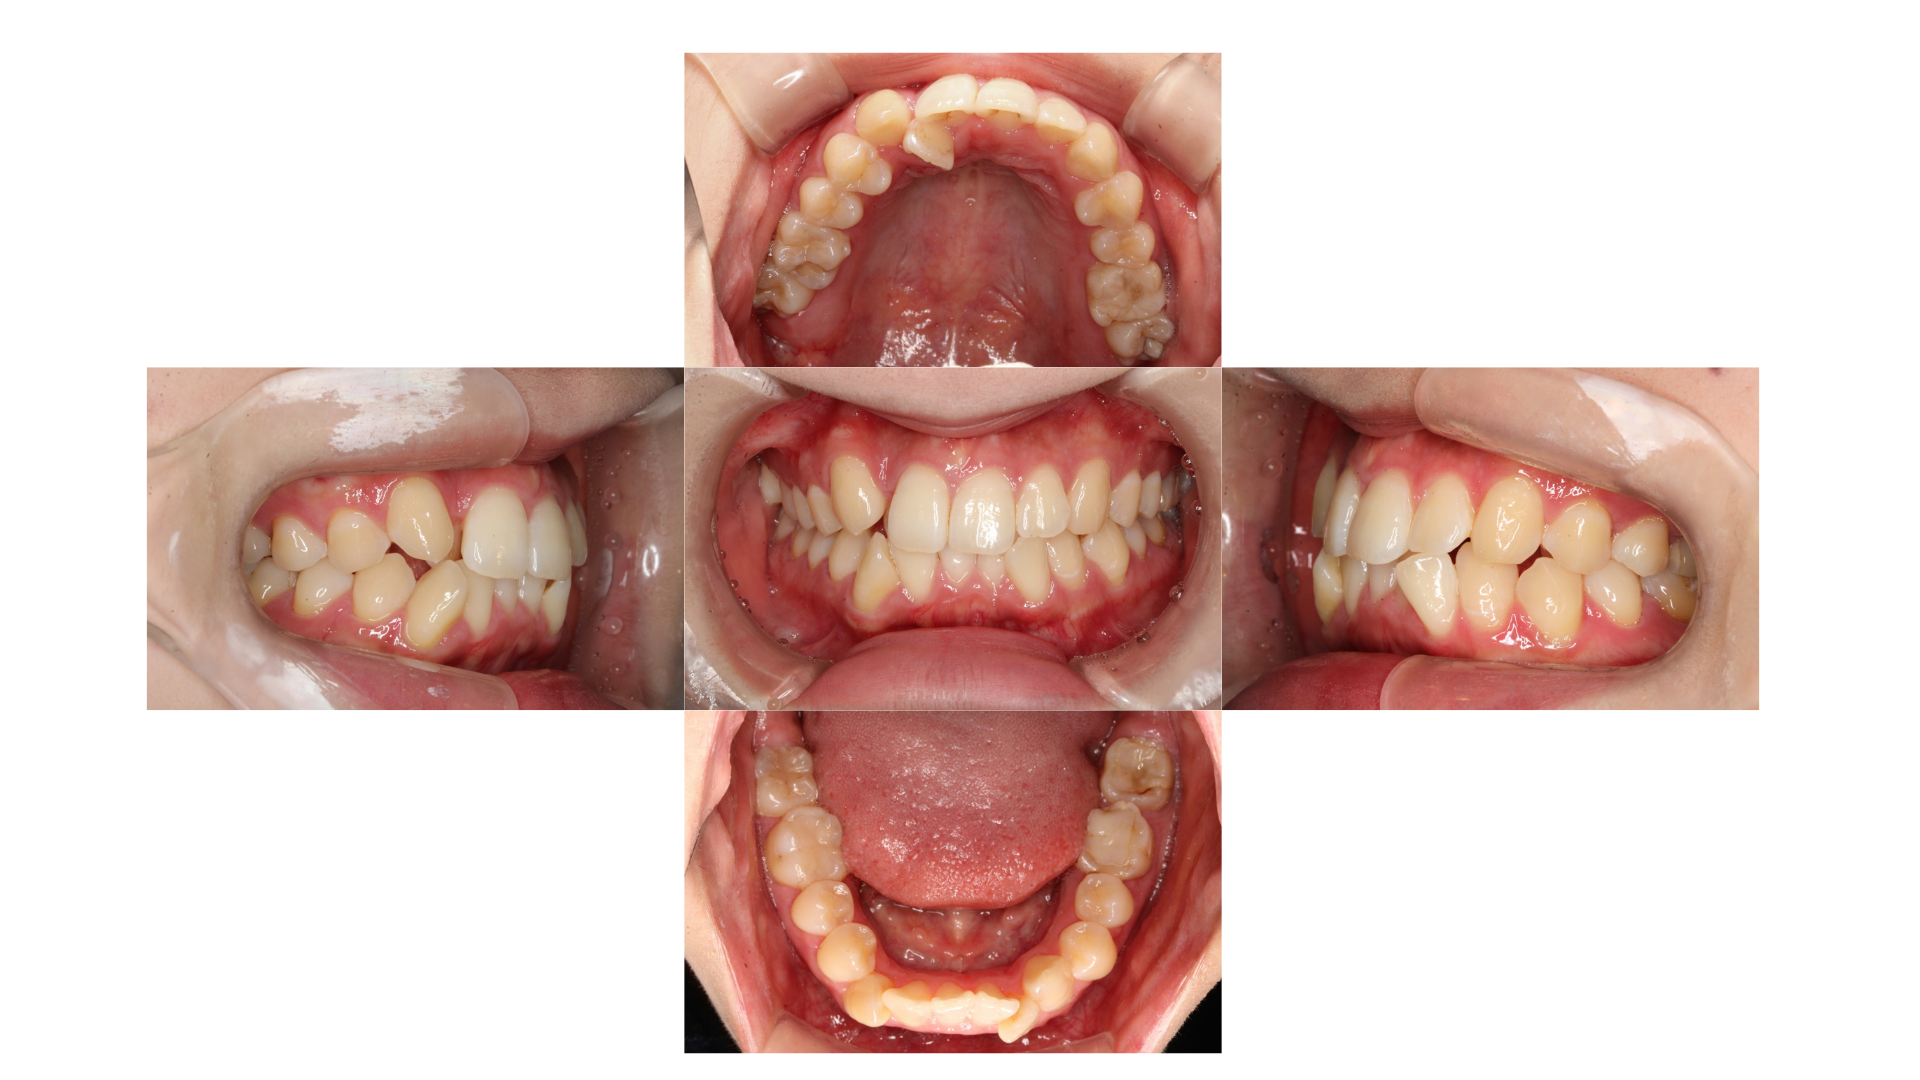

八重歯が気になる(約1年1ヵ月/通院:20回)

| 主訴 | 【主訴】八重歯 【診断・症状】低位唇側転位 |

| 抜歯 | 有(上4,4、下4,5) |

| 矯正の装置 | 裏側矯正(舌側矯正) |

| 副作用・リスク | 歯肉退縮,歯根吸収,疼痛,咬合の違和感,装置の違和感,虫歯,歯肉炎 |